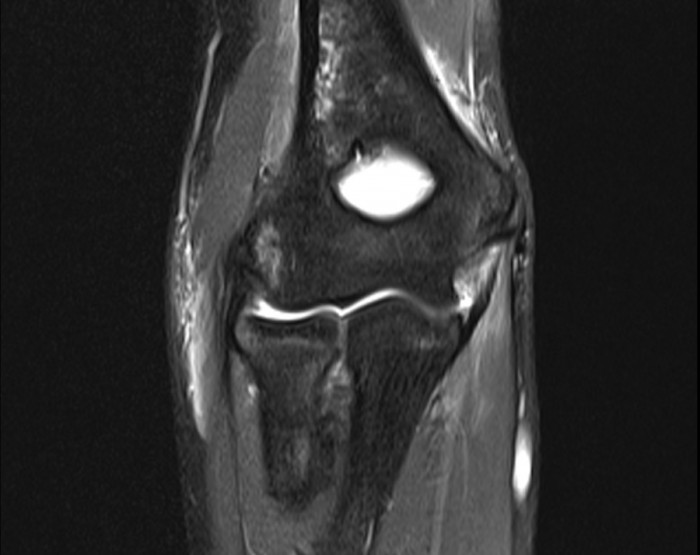

From www.mri.melbourne

mrielbowmedialcollateralligamentinjury MRI at Melbourne Golfers Elbow Ligament Tear It has also been referred to as “medial. Golfer's elbow is a condition that causes pain where the tendons of your forearm muscles attach to the bony bump on the inside of your elbow. Magnetic resonance imaging is the ideal standard for diagnosis of medial epicondylitis but generally is used to rule out other possible causes of medial elbow pain.. Golfers Elbow Ligament Tear.

Ulnar Collateral Ligament Elbow Mri Golfers Elbow Ligament Tear Golfer’s elbow, known medically as medial epicondylitis, is a form of tendonitis that causes pain and inflammation in the tendons. Golfer's elbow is a condition that causes pain where the tendons of your forearm muscles attach to the bony bump on the inside of your elbow. Golfer’s elbow, also known as medial epicondylitis, is a painful condition that occurs when. Golfers Elbow Ligament Tear.